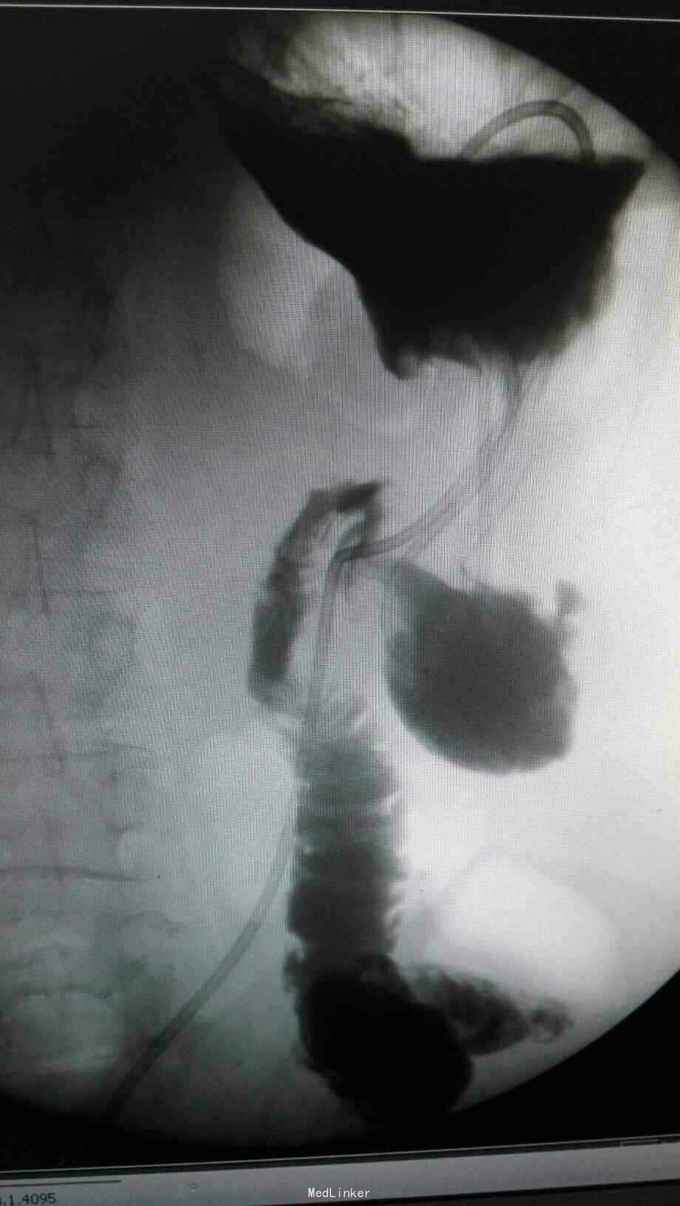

查体:入院后查体腹部平软,未见胃肠型,上腹部正中部可见20cm陈旧性瘢痕,腹部无压痛及跳痛,无肌卫;叩诊鼓音,肝脏及脾脏肋下未及;肝肾区无叩击痛,移动性浊音阴性,肠鸣音弱,1-2次/分。 检查:本次入院后查:WBC:9.2*10^9/L,Na:132mmol/L,余指标基本正常。电子胃镜:胃大部切除术后改变(毕II)吻合口粘膜充血水肿明显,直径约1.2cm,分别尝试进入输入袢及输出袢,见肠腔无明显狭;上腹部增强CT:1胰十二指肠切除术后;2肝脏多发小囊肿;3腹腔内未见明显感染及肿瘤转移征象。上消化道造影:残胃形态、扩张可,未见明显潴留液,蠕动较弱,中远部充盈不佳,胃小肠吻合口宽约1.2cm,未见狭窄及碘水渗漏。胃排空较慢。